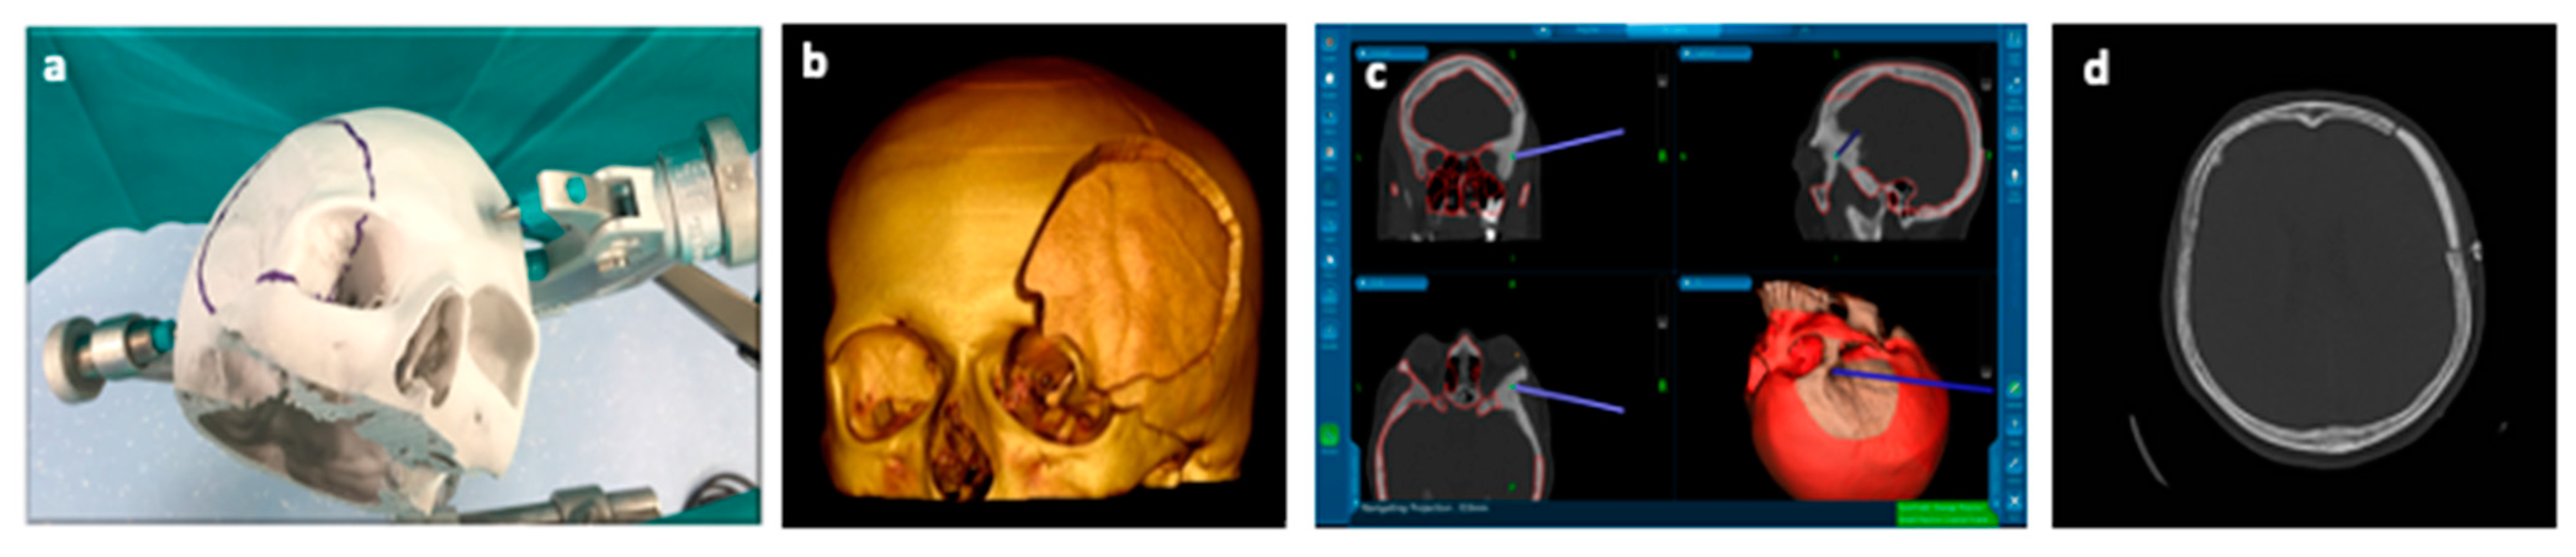

These 3D printing technologies are already used in clinical practice. One example is the one-step procedure that consists of a single surgical operation comprising a resection and reconstruction of cranial defects for lesions involving the skull base [71]. An example is reported in Figure 7:

Figure 7.

(a) Phantom model for virtual craniotomy; (b) 3D HR CT-scan of Phantom; (c) stealth navigation station; (d) post-operative axial CT-scan.

This procedure takes advantage of virtual 3D skull modelling techniques (Phantom model) (Figure 7a) by acquiring the patient’s high resolution (HR) CT-scan (Figure 7b) and creating a tailored cranioplasty, which reproduces an accurate reconstruction of the bone defect. To achieve better results modern stealth navigation assists the surgeon to perform the craniotomy and match to the custom-made cranioplasty (Figure 7c,d) [20].